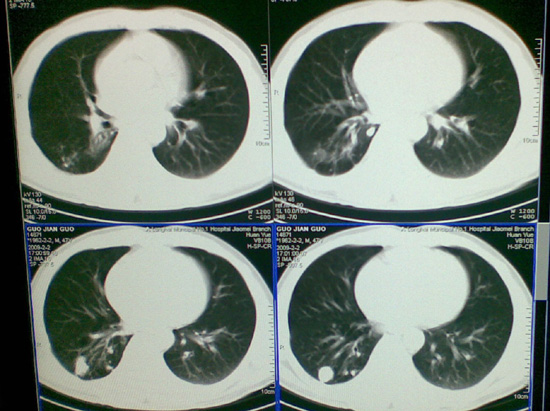

像肺结核钙化吗,不曾见过的影像,请大家帮忙看一下

陈旧性肺结核,钙化。

右肺结核(以纤维增殖、钙化病灶为主)。